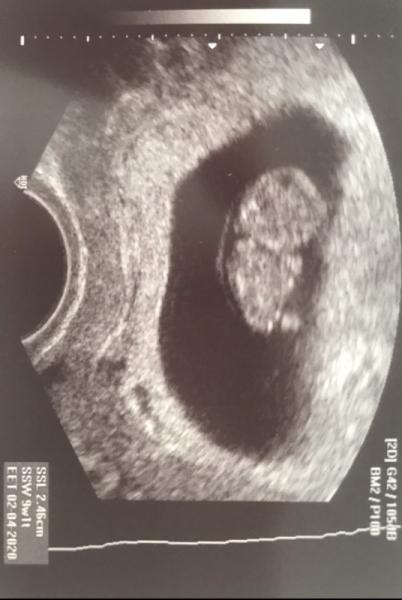

Endlich durften wir heute auch unser Pünktchen das erste mal sehen und alles ist in bester Ordnung Herzchen schlägt kräftig und hatte auch schon eine Grösse von ca 2,5 cm In zwei Wochen soll ich nochmal hin

Bild zu Zurück vom FA - Forum für April - Mamis